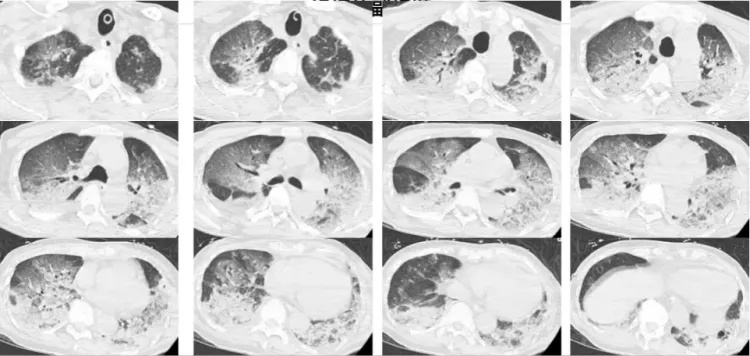

接诊后,韩爷爷意识不清,血压、心率下降,医生们一度怀疑其有肺栓塞或脑梗 ,于是立即为他进行头颅、胸部CT和肺血管CTA检查。

可结果一出来,医生们吓了一跳,韩爷爷的双肺全白了 !

医生检查后排除了他脑中风和肺栓塞的可能,那么,什么病能导致这么大面积的白肺?

经会诊,最终韩爷爷被确诊为热射病诱发的肺水肿。